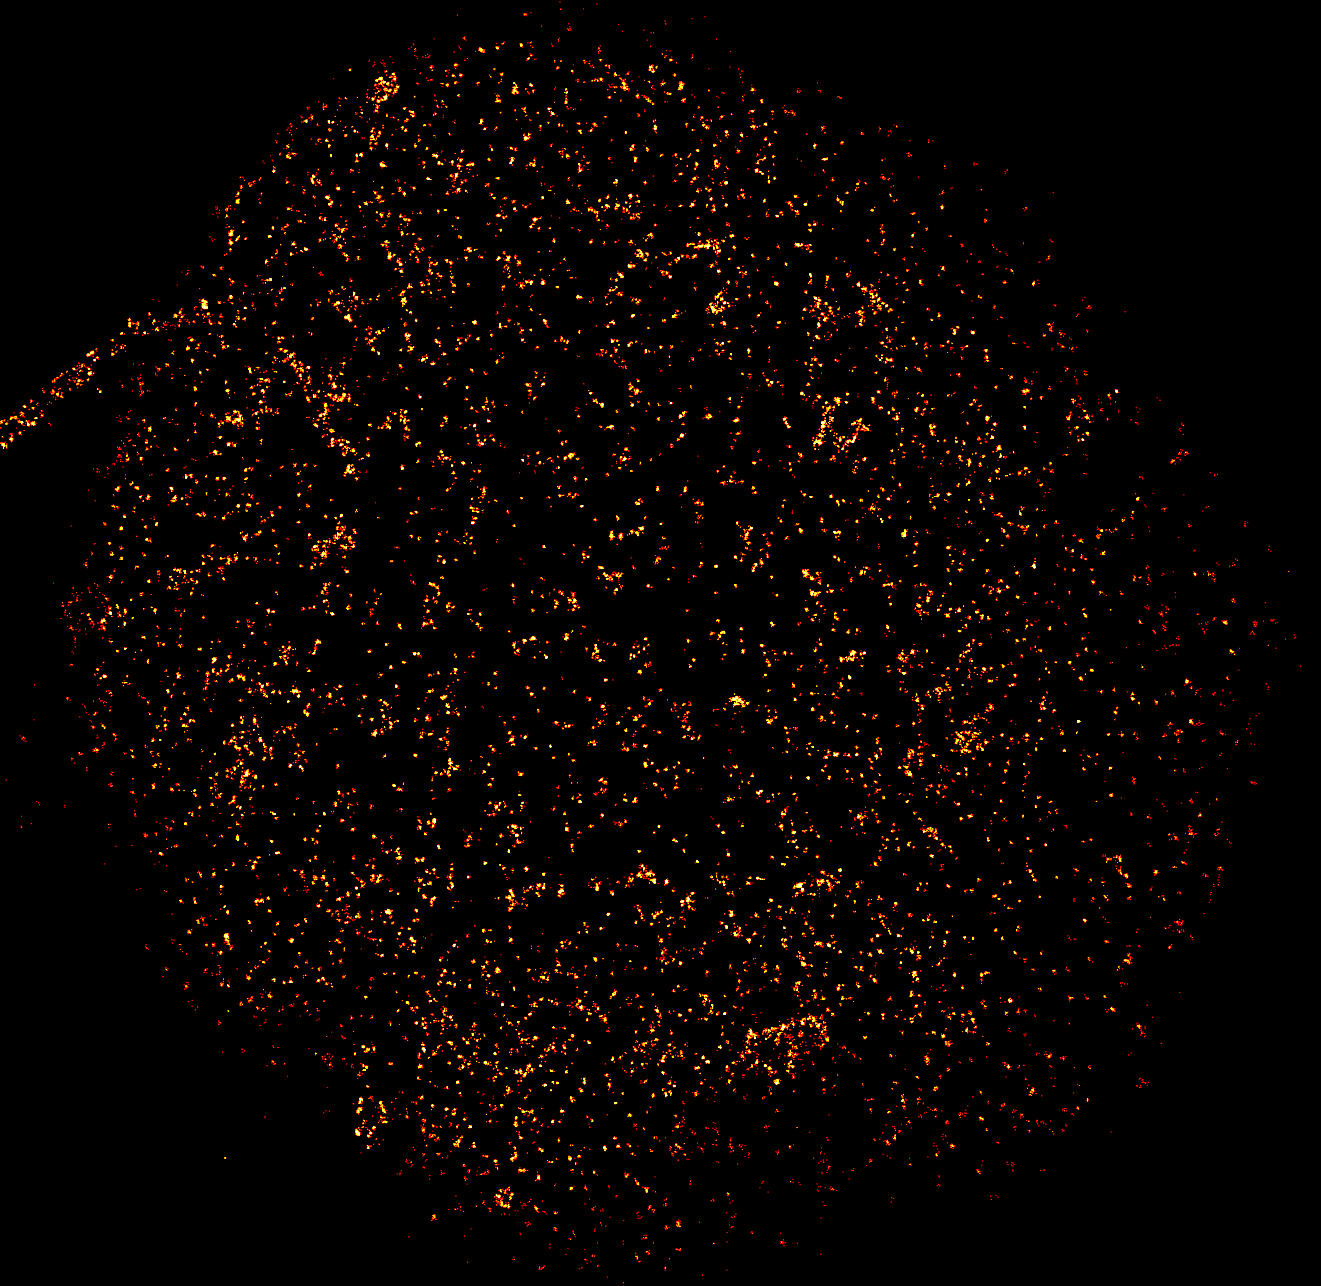

Multimodale durchflusszytometrische Analyse von Proben von Studienteilnehmenden, die am Multiplen Myelom oder eines seiner Vorstufen erkrankt sind

Bei den Proben handelt es sich um Blut von Patientinnen und Patienten, die am MM, beziehungsweise eines seiner Vorstufen erkrankt sind. Neben archivierten Proben, die in der Interdisziplinären Biomaterial- und Datenbank Würzburg (ibdw) kryokonserviert, also in flüssigem Stickstoff eingefroren sind, werden im Rahmen und im Zeitraum des geförderten Projekts neue Proben gewonnen. Neben Alter und Geschlecht werden klinische Daten wie Zahl und Art der Vorbehandlungen sowie der Krankheitsverlauf erfasst. Für die genomische Charakterisierung der Myelomzellen spielt unter anderem die Durchflusszytometrie eine große Rolle.

Die Durchflusszytometrie ermöglicht eine hochempfindliche Tumordiagnostik. In Echtzeit können die Krankheitsbelastung und das Immunprofil des Betroffenen gemessen werden, was wiederum wertvolle Informationen über das Ansprechen der gewählten Therapie gibt. Das Team von Prof. Dr. Dr. Andreas Beilhack aus der Medizinischen Klinik und Poliklinik II führt seit mehr als zwei Jahren bei Patientinnen und Patienten mit MM regelmäßig Knochenmark- und Bluttests mit Durchflusszytometrie durch. „Mit diesem deutschlandweit einzigartigen Bluttest sind wir jetzt schon in der Lage routinemäßig eine Myelomzelle unter einer Million gesunder Blutzellen zu erkennen. Aktuell verfeinert Dr. Paula Tabares aus meinem Team diese Methode weiter, und kann jetzt schon eine Myelomzelle unter 100 Millionen nachweisen“, berichtet der Mediziner und Immunologe.